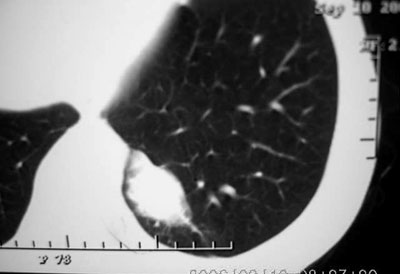

左侧脊柱旁沟可见一边界清,密度不均匀之块状影,其内可见水样低密度影。

2、病变位于左肺下叶后段,周围肺组织相对干净,没有明显异常的改变,基本可以排除炎性病变;病变实质内密度均匀,边缘清晰,后下缘与膈脚分界不清晰。各征象均支持肺隔离症。

左下叶后基底段内胸主动脉旁可见一类梭形团块状影,边界较清楚,其内有小结节样高密度钙化影,肿块与胸主动脉可见条状影相连(见下图).

把选定的图像复制到woad,左键双击--图片设计格式--图片--亮度,调整亮度(到60--70)即可见到病灶血管与降主动脉相连,即病灶由降主动脉供血.